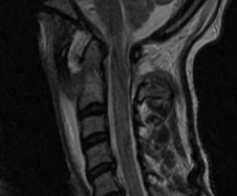

A 27-year-old male patient with no relevant medical or surgical history and working in the military army, was observed in an Orthopedics consultation, referred from primary health care for complaints of neck pain, without irradiation to the upper limbs, associated with limitation of mobility, especially in sagittal plane movements, with 4 months of evolution (Neck Disability Index (NDI) of 26). The patient denied a history of trauma, but reported upper respiratory infection (pharyngitis) one month before the onset of cervical pain. Physical examination revealed decreased cervical mobility, without other major findings. The diagnostic study began with two-plane cervical radiography (Figure 1), with an approximate ADI value of 10.5 mm, as well as dynamic radiographs (Figure 2), which demonstrated C1-C2 dynamic instability (ADI of 10.9 and 9.8 mm respectively). The CT study confirmed atlanto-axial sub dislocation and excluded the presence of fractures or facet subluxations (Figure 3). The study was complemented by magnetic resonance imaging, which confirmed atlanto-axial sub dislocation, associated with inflammation and thickening of the paravertebral soft tissues, with transverse ligament incompetence (Figure 4 - magnetic resonance imaging). Due to the decreased mobility of the upper cervical spine, the possibility of Meningitis was raised. Blood analytical study showed marginal elevation of C-Reactive Protein (28 mg/L), thus, the hypothesis of Grisel's Syndrome was placed. The patient was initially treated with the use of a Minerva cervical collar and broad-spectrum empirical antibiotic therapy with Ceftriaxone for 6 weeks, but after this period, there was unfavorable clinical evolution, with worsening of cervical pain and functional status (NDI of 30). Surgical treatment was therefore elected, through posterior atlanto-axial fixation, which is in accordance with other cases published in the literature.2The surgery was uneventful and the patient had a favorable clinical course, with significant improvement in neck pain and joint mobility, with an improvement in the NDI from 30 to 5. Radio graphically, a reduction in atlanto-axial subluxation was confirmed (Figure 5), which remained stable until 5 years of follow-up. There were no late complications and the patient resumed his normal activities.

Figure 4 – Magnetic Ressonance image showing C1-C2 inflamatory tissue.